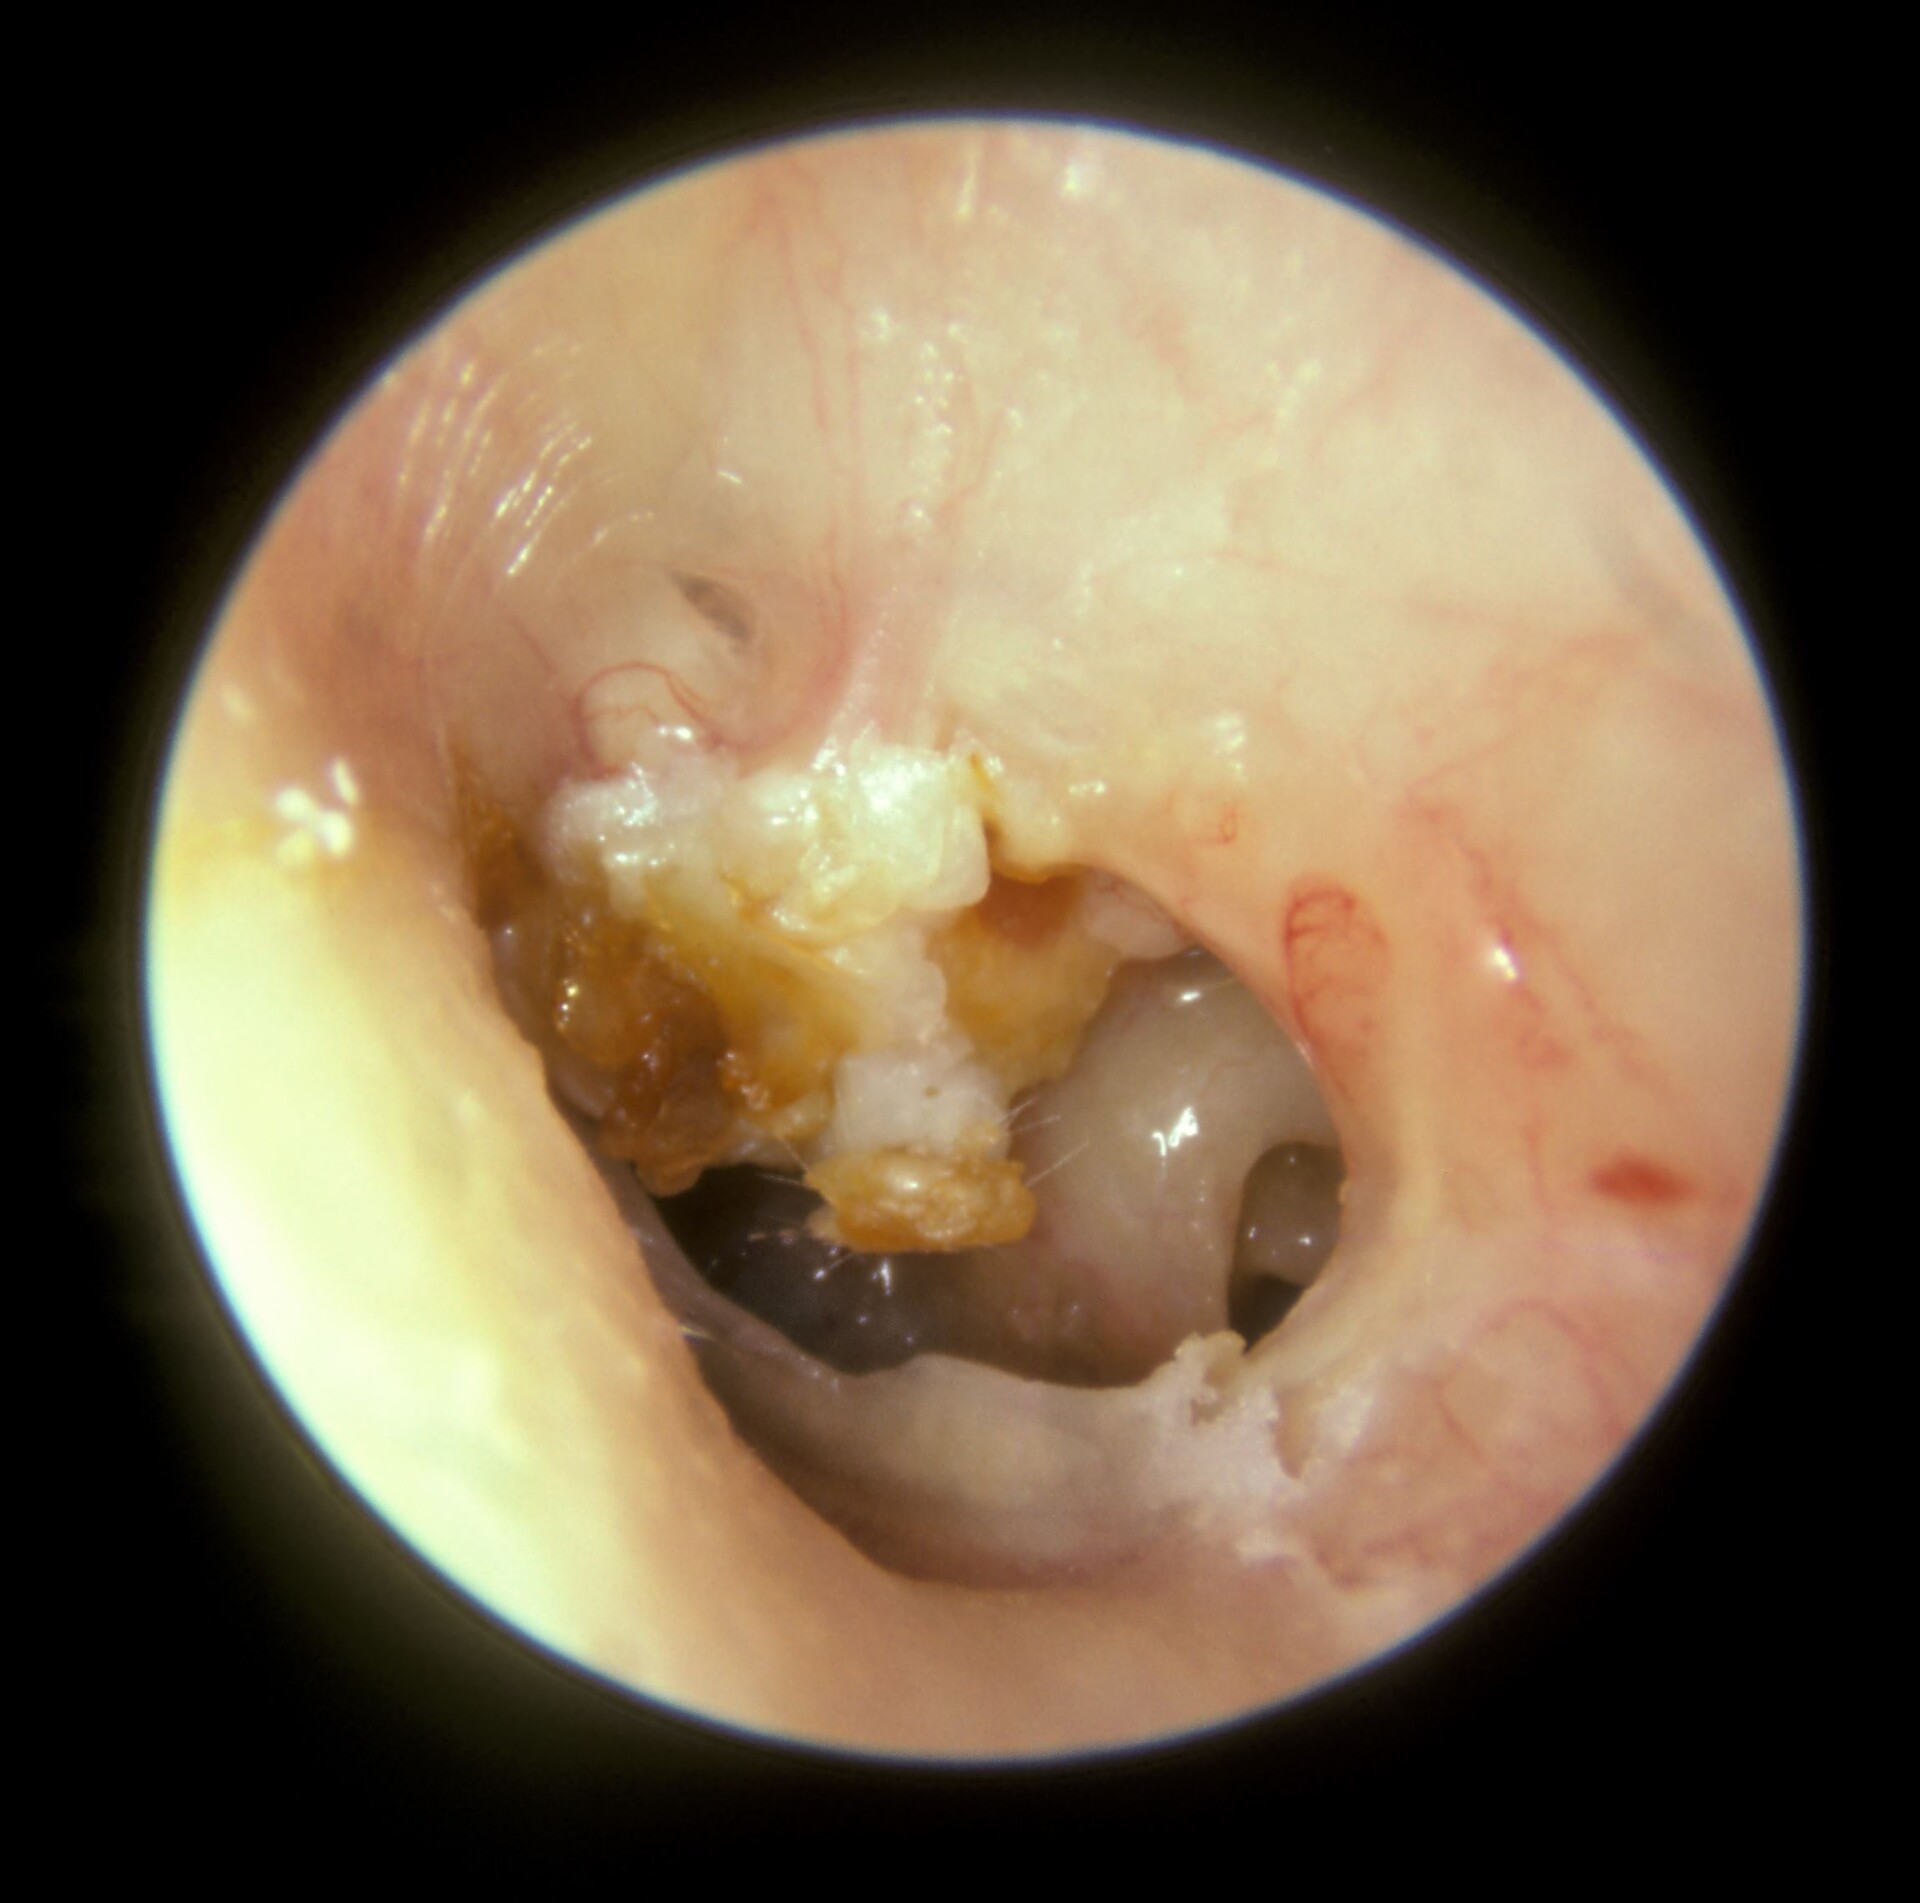

Cholesteatoma Cyst in Middle Ear Benign Ear Cyst

Images of primary cholesteatoma of the right middle ear cavity (a What Is A Cholesteatoma Of The Middle Ear cholesteatoma is an abnormal skin growth or skin cyst trapped behind the eardrum, or the bone behind the ear. They're rare but, if left untreated, they can damage the. a cholesteatoma is an abnormal collection of skin cells deep inside your ear. cholesteatomas are benign but expansive aggregations of keratinized squamous debris within the middle ear, which. What Is A Cholesteatoma Of The Middle Ear.